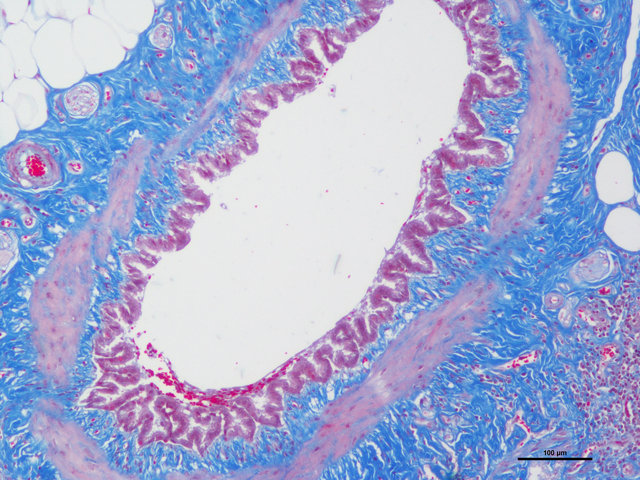

胶原纤维呈蓝色;胞质、肌纤维、红细胞呈红色;胞核黑蓝色。

样片参考: